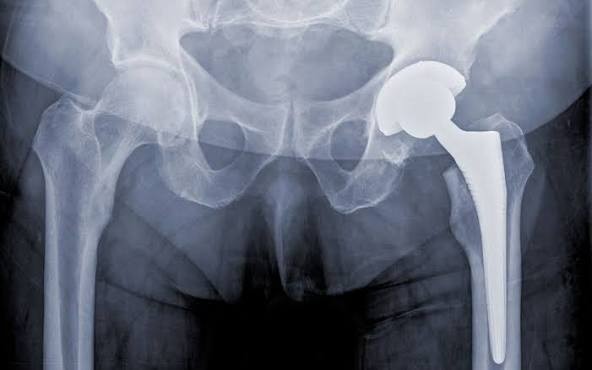

A total hip replacement (THR), also known as total hip arthroplasty, is a common surgical procedure in which damaged surfaces of the hip joint are replaced with artificial components made of metal, ceramic, or plastic. The surgery is performed to relieve pain, reduce stiffness, and improve mobility, most often due to severe arthritis or injury.

- Materials: Components are made from metal, ceramic, and plastic.

- Fixation: Implants may be cemented or press-fit, allowing bone to grow into a porous coating.

- Lifespan: Modern hip implants often last 15–25 years or longer.